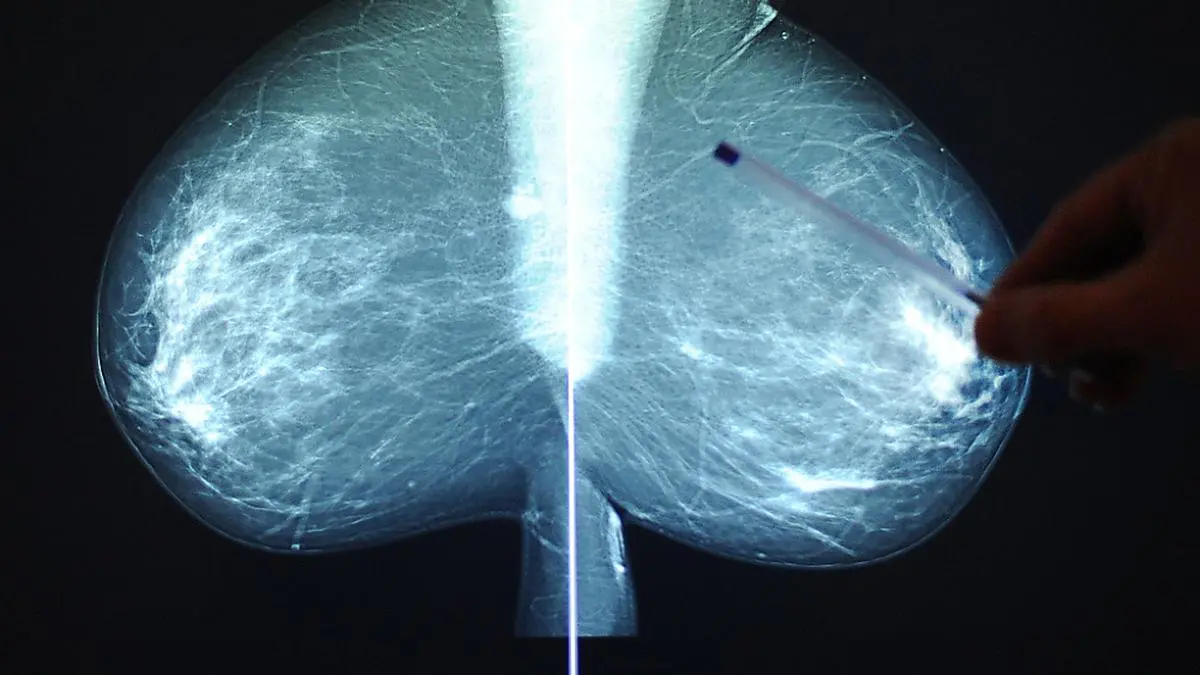

Brustkrebs bei früher Diagnose immer besser behandelbar

Jede achte Frau in Österreich erkrankt im Lauf ihres Lebens an Brustkrebs. Das bedeutet rund 5.600 Neudiagnosen pro Jahr. Je früher der Krebs erkannt wird, desto besser ist die Fünf-Jahres-Überlebensrate, erläuterte Marija Balic vom LKH/Universitätsklinikum Graz am Mittwoch bei einer Pressekonferenz des Pharmaunternehmens Gilead in Wien. Dort wurde anlässlich des Brustkrebs-Monats Oktober an die Wichtigkeit der Früherkennungsuntersuchung und der Selbstkontrolle erinnert.